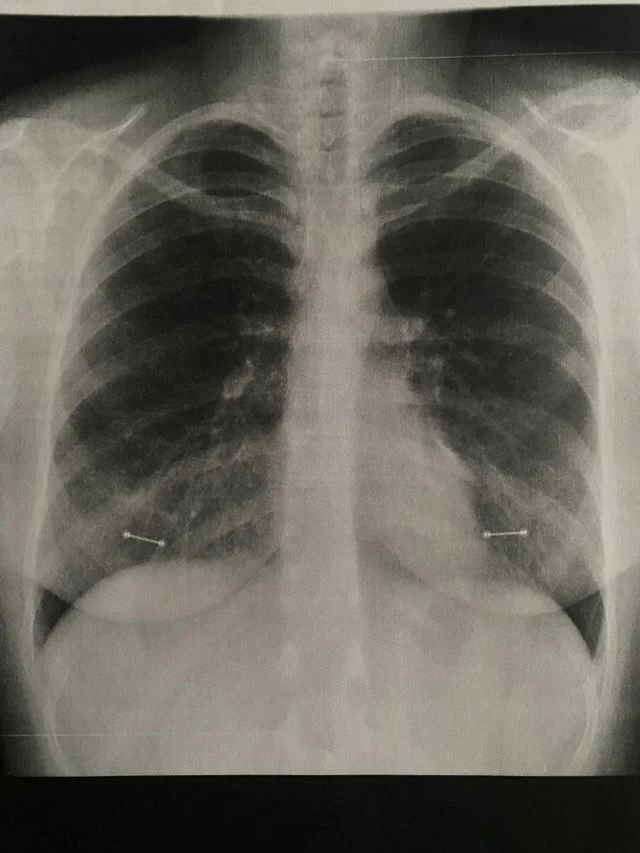

Сережки на снимке